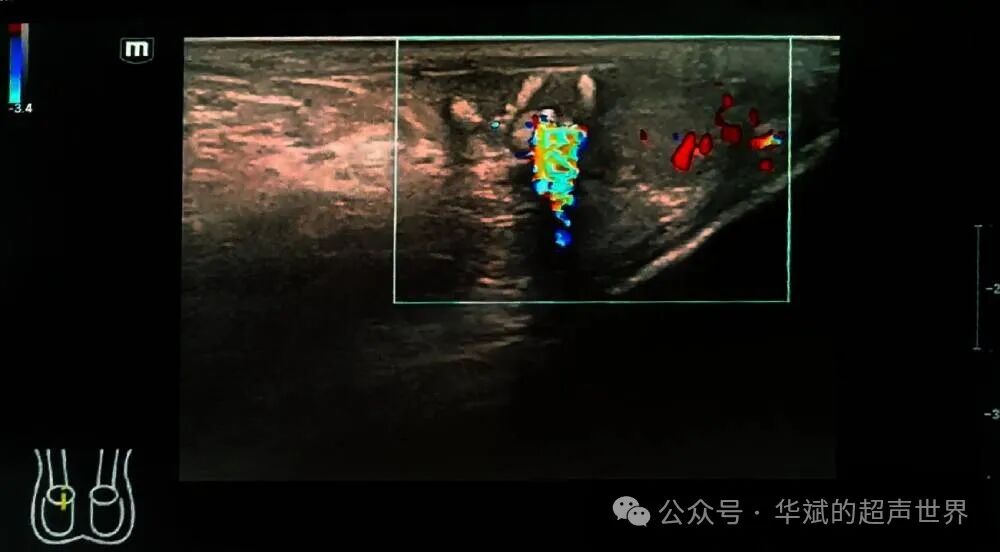

youyuanzhiren 问:华斌老师您好!最近遇见一个夜间急诊病人,27岁,腹股沟区疼痛难忍来就诊的患者,查看泌尿系彩超是正常的,血常规,尿常规没问题。超声检查双侧睾丸未见异常,左侧附睾头囊肿,右侧附睾头可见多发的强回声团,后伴声影和快闪伪像,这种考虑结石吗,后面随访说医生开了点止痛跟消炎药回家吃了第二天就没事了,请老师您帮忙看看!

附睾内的结石较少见,也偶尔有输精管和精囊内的游离结石的报道,尽管这些结构的壁的钙化更为常见。附睾小结石可能是由于精子的凝集和随后的钙化,或慢性炎症过程的结果。

与前列腺内的结石一样,附睾内的结石聚集后在超声的声像图上同样伴有明显的快闪伪像。

通常情况下附睾结石是无症状的。部分附睾结石可能与附睾炎有关,会伴有附睾睾丸疼痛的症状。本例患者的腹股区疼痛可能与附睾炎的急性发作有关,不过由于提供的图片相对比较少,不好确定。